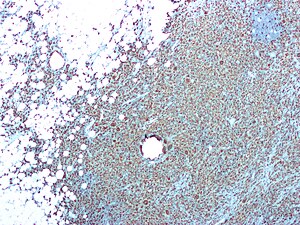

Xanthogranulomatous pyelonephritis. CD68 immunostain. | |

| IHC | CD68 +ve, CD10 -ve, pankeratin -ve |

- CD68 +ve.

RIGHT KIDNEY, NEPHRECTOMY: - XANTHOGRANULOMATOUS PYELONEPHRITIS. - CHRONIC INTERSTITIAL NEPHRITIS. - INCREASED NUMBERS OF TOTALLY SCLEROSED GLOMERULI AND GLOMERULI WITH FOCAL SCLEROSIS. - MARKED INTERSTITIAL FIBROSIS. - NEGATIVE FOR MALIGNANCY. COMMENT: Immunostaining demonstrates abundant CD68 positive cells (macrophages). A CD10 immunostain is non-concerning (it highlights glomeruli). A pankeratin immunostain is non-concerning (it highlights benign renal tubules).